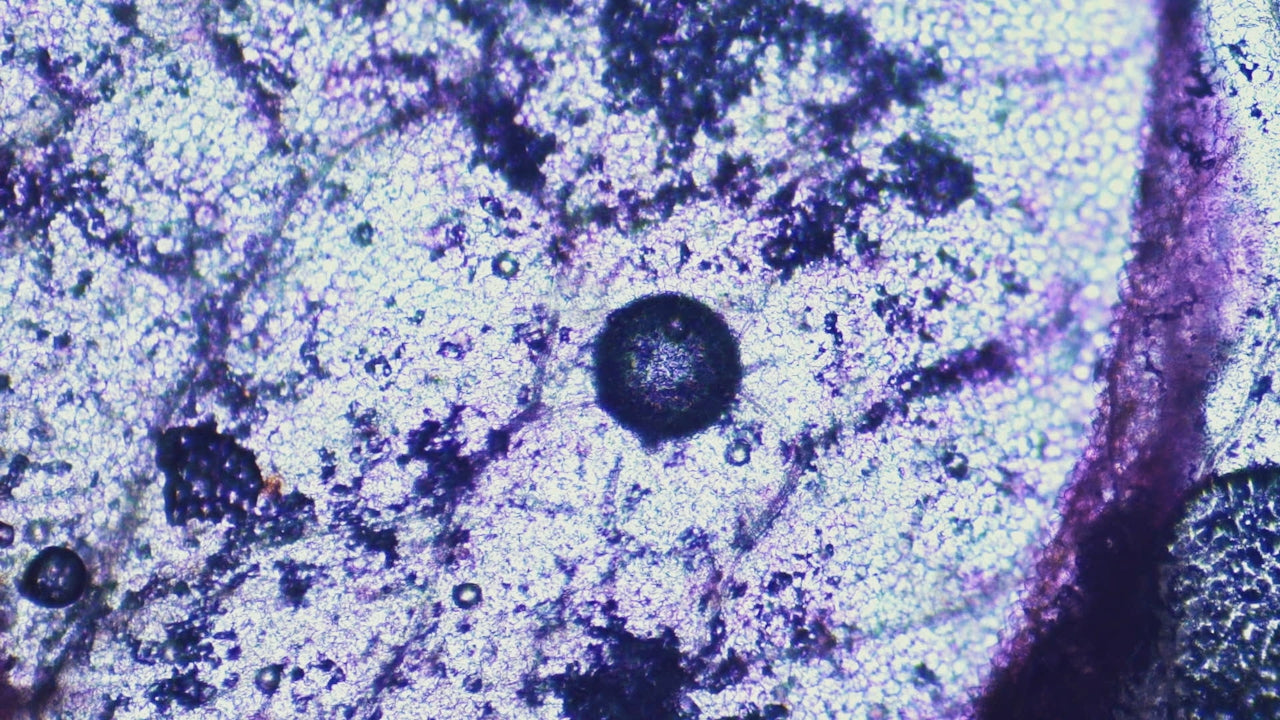

Short-Chain Fatty Acids (SCFAs): Why They’re Central to Gut Microbiome Health

Short-chain fatty acids are produced when gut microbes ferment fibre in the colon. They support gut barrier integrity, immune signalling, and reflect active microbial metabolism. Because SCFAs are ...